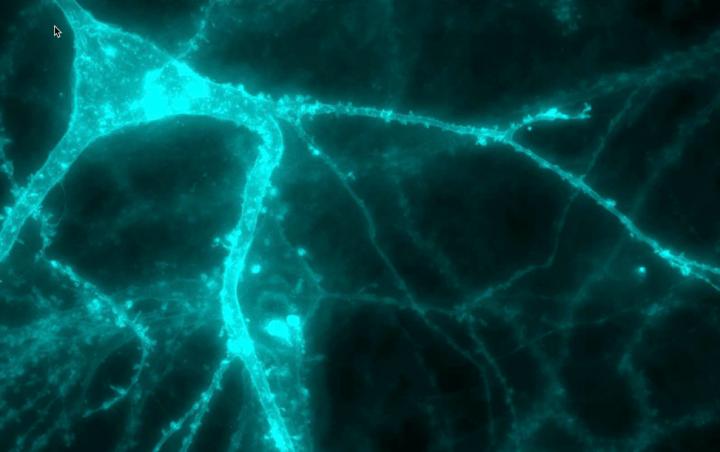

In preliminary experiments to test the drug's potential, the researchers used a technique devised by Loren Looger, a group leader at HHMI's Janelia Research Campus, to make neurons in culture fluoresce when they release neurotransmitters. Neurons containing mutated syt1 proteins flashed only dimly under the microscope. But adding 4-AP boosted their fluorescence.